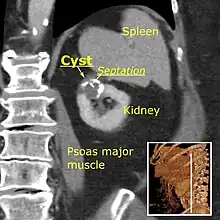

- Bosniak II cyst at the lower pole of right kidney with septations within.